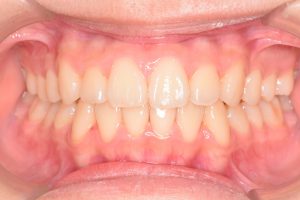

正面

0000000001

0000000022

0000000073